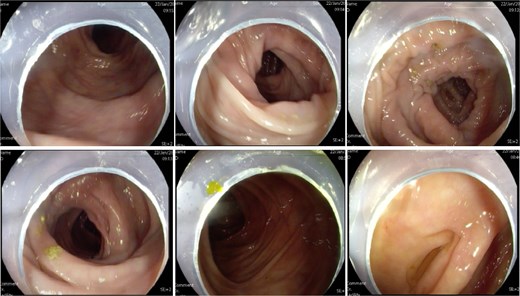

A 60-year-old female presented with a 3-year history of progressively worsening defecatory dysfunction characterized by prolonged straining (⁓15 min per episode), incomplete evacuation, and reliance on manual vaginal pressure to facilitate stool expulsion. Despite daily bowel frequency (twice per day), stools remained soft-formed but impacted at the anal verge. Physical examination in the lithotomy position revealed no anal fissures or sphincteric abnormalities (no evidence of sphincter hypotonia or hypertonia on digital rectal examination). A palpable rectovaginal bulge was identified during digital assessment, while proctoscopy demonstrated no intraluminal lesions. Routine laboratory investigations—including complete blood count, fasting glucose, hepatic/renal function panels, coagulation studies, electrolyte profiles, infectious serologies, and electrocardiography—were unremarkable. Colonoscopy excluded organic colorectal pathology (Fig. 1).

Colonoscopy showed no abnormal lesions in the bowel after admission.